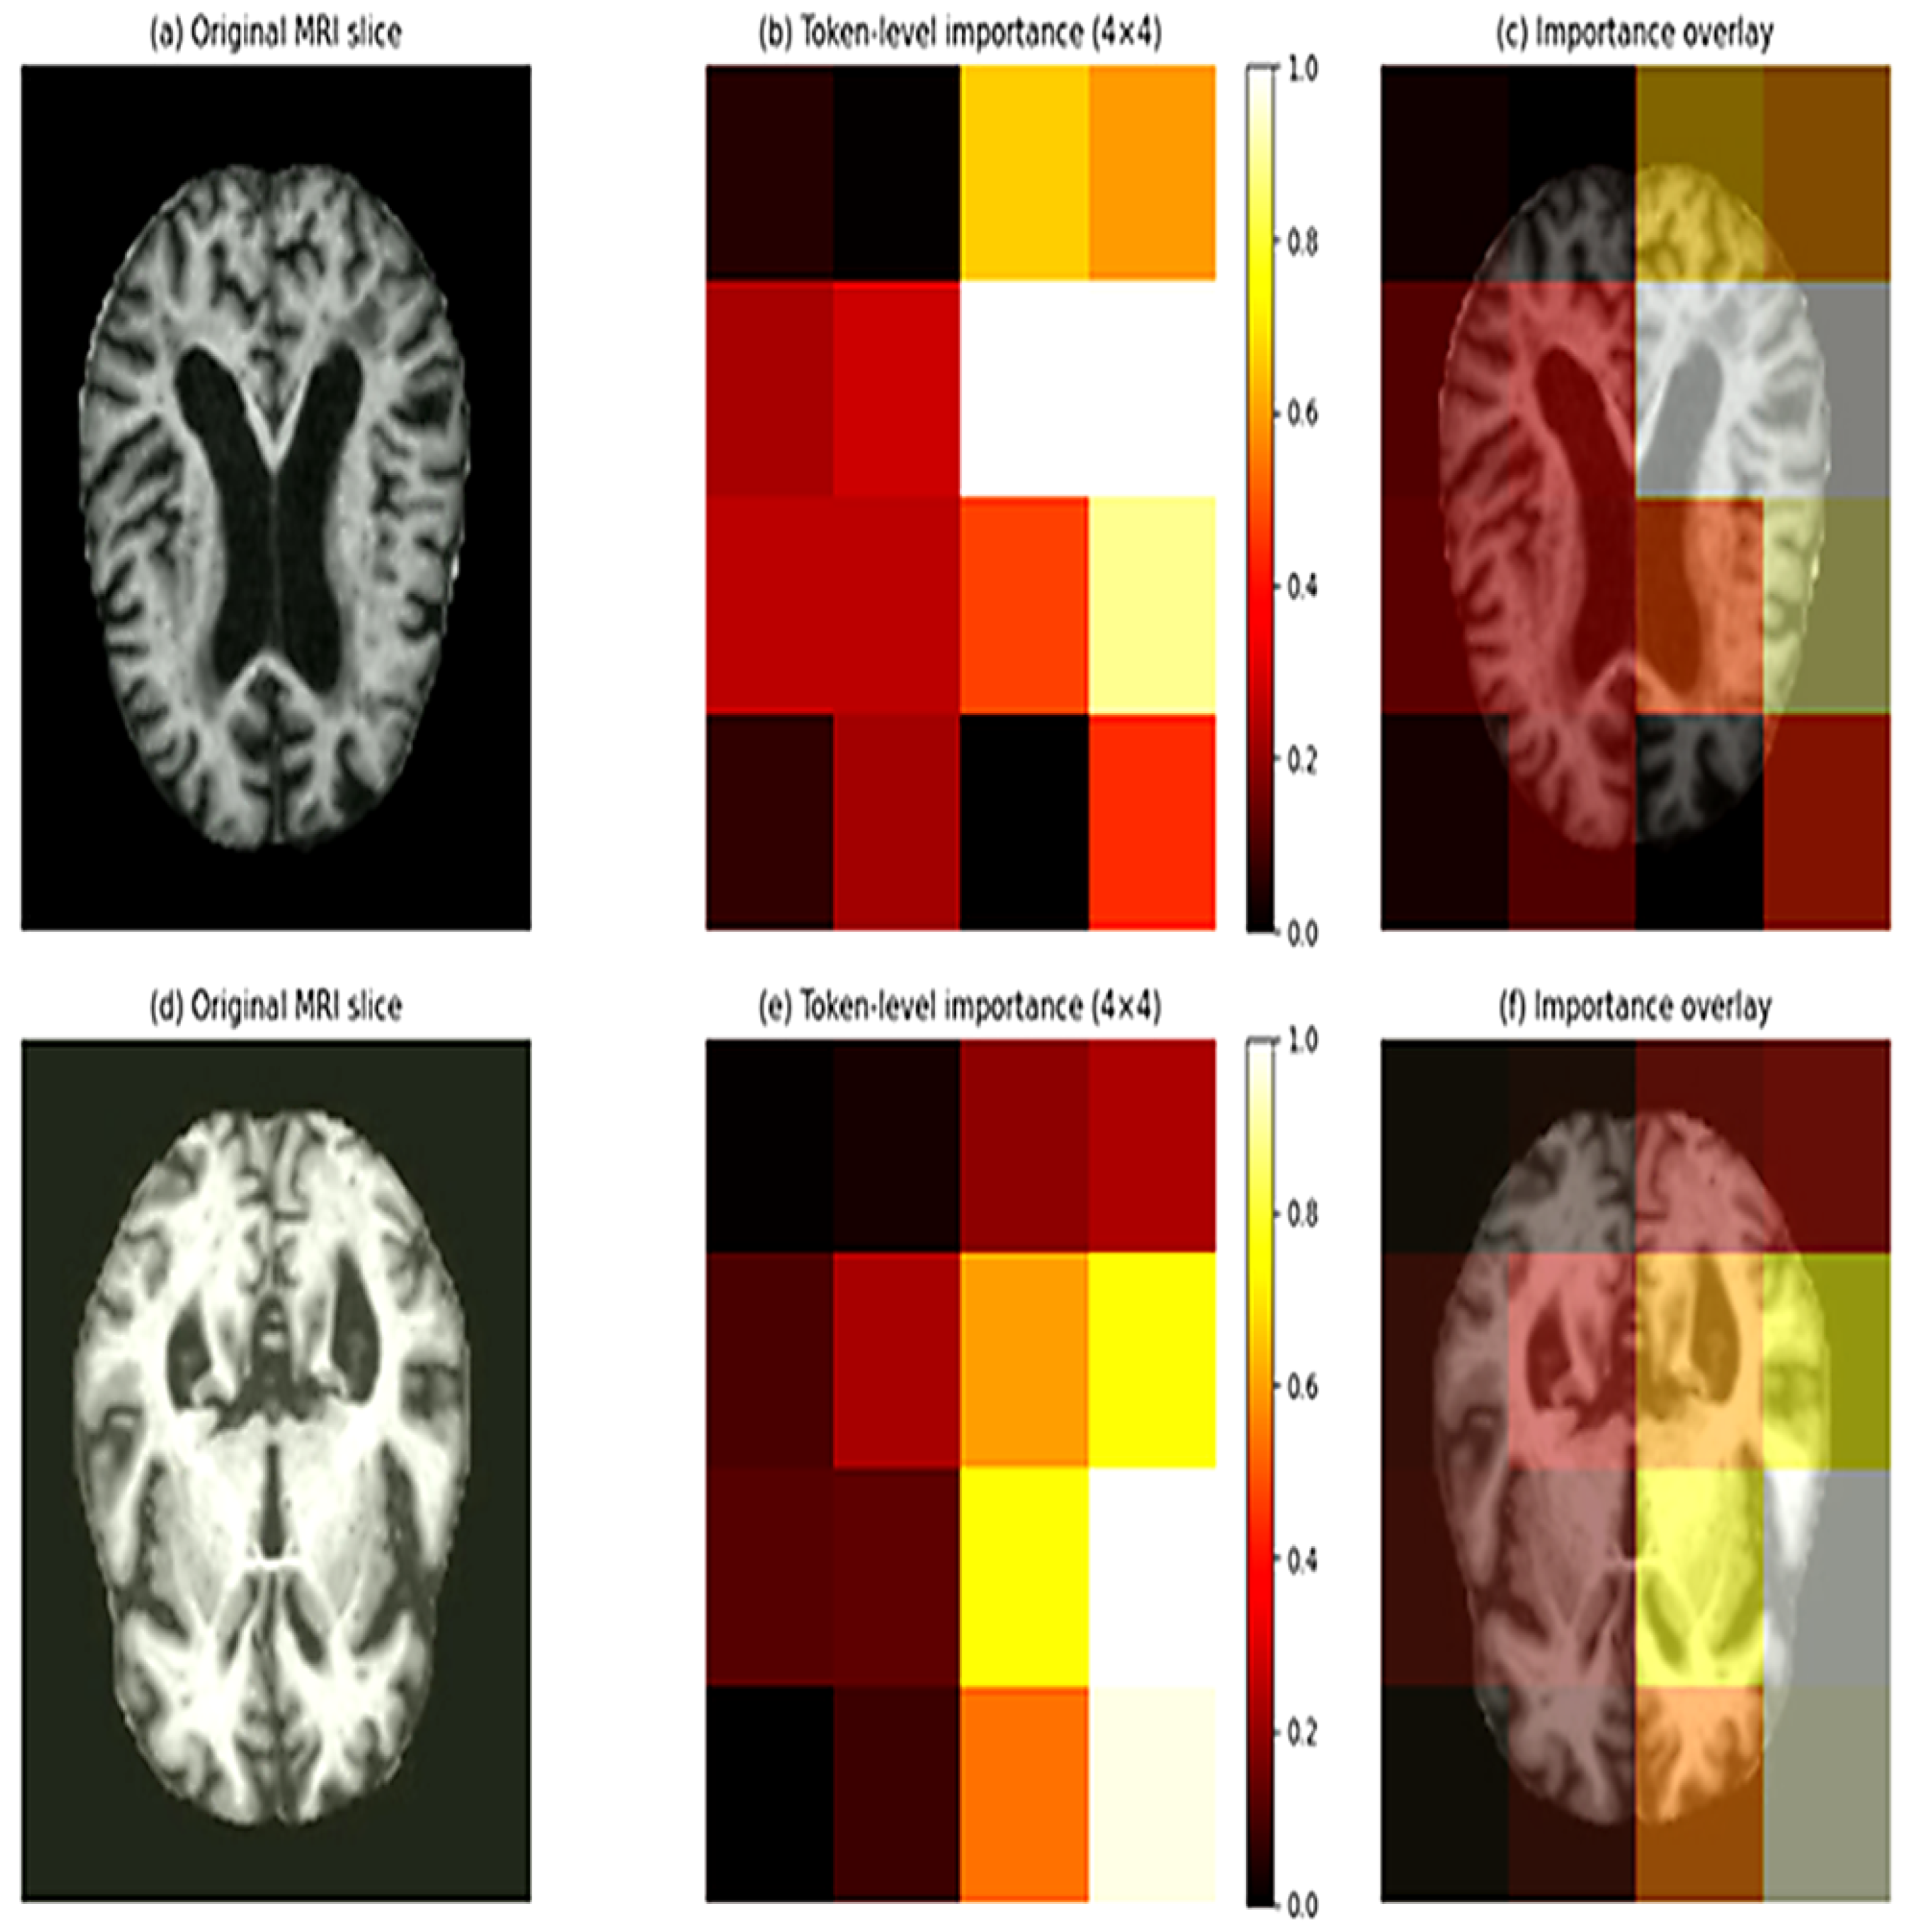

- We provide token-level interpretability analysis to improve transparency and trust in model decisions.

3.9. Model Interpretability via Token Importance

4.2. Token-Level Interpretability and Disease Progression Analysis